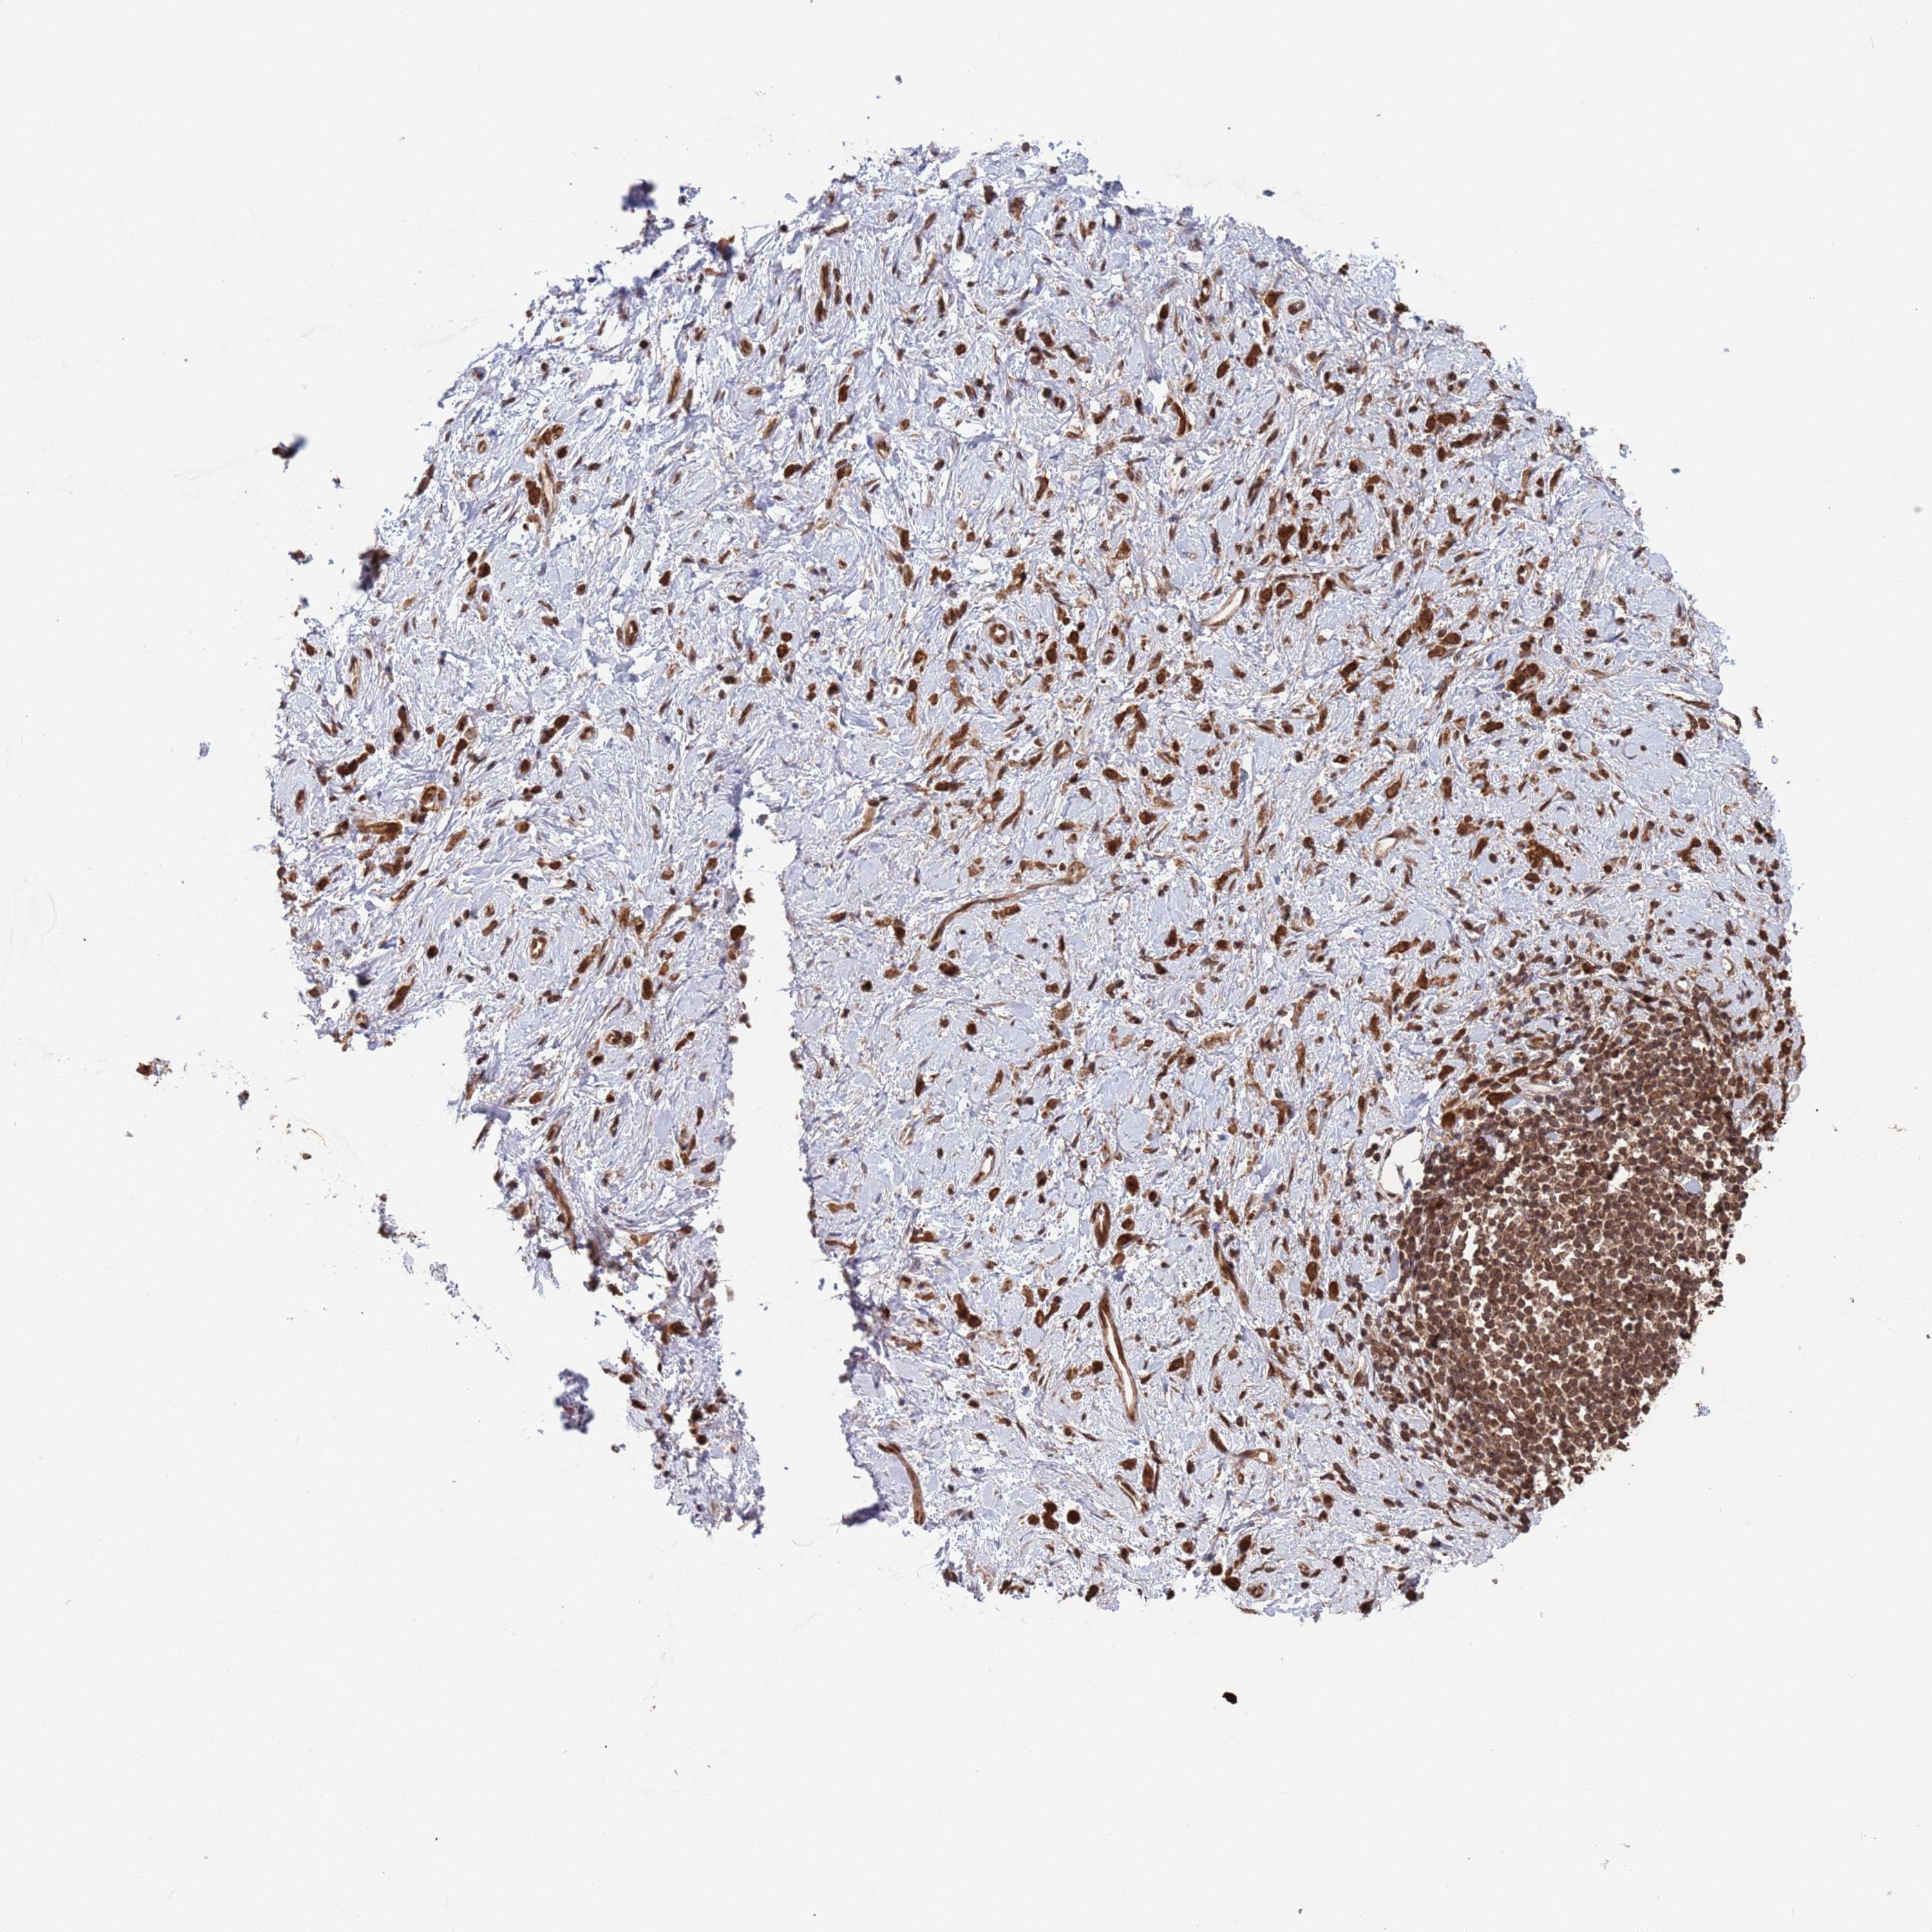

STOMACH CANCER - Protein expressioni

A mouse-over function shows sample information and annotation data. Click on an image to view it in a full screen mode. Samples can be filtered based on level of antibody staining by selecting one or several of the following categories: high, medium, low and not detected. The assay and annotation is described here.

Antibody stainingi

Antibody staining in the annotated cell types in the current human tissue is reported as not detected, low, medium, or high, based on conventional immunohistochemistry profiling in selected tissues. This score is based on the combination of the staining intensity and fraction of stained cells.

Each image is clickable and will lead to virtual microscopy that enables deeper exploration of all samples and also displays staining intensity scores, fraction scores and subcellular localization as well as patient and tissue information for each sample.

Antibody HPA047658

Antibody HPA058392

Staining

High

Medium

Low

Not detected

Intensity

Strong

Moderate

Weak

Negative

Quantity

>75%

75%-25%

<25%

None

Location

Nuclear

Cytoplasmic/membranous

Cytoplasmic/membranous,nuclear

Adenocarcinoma, NOS

Adenocarcinoma, High grade